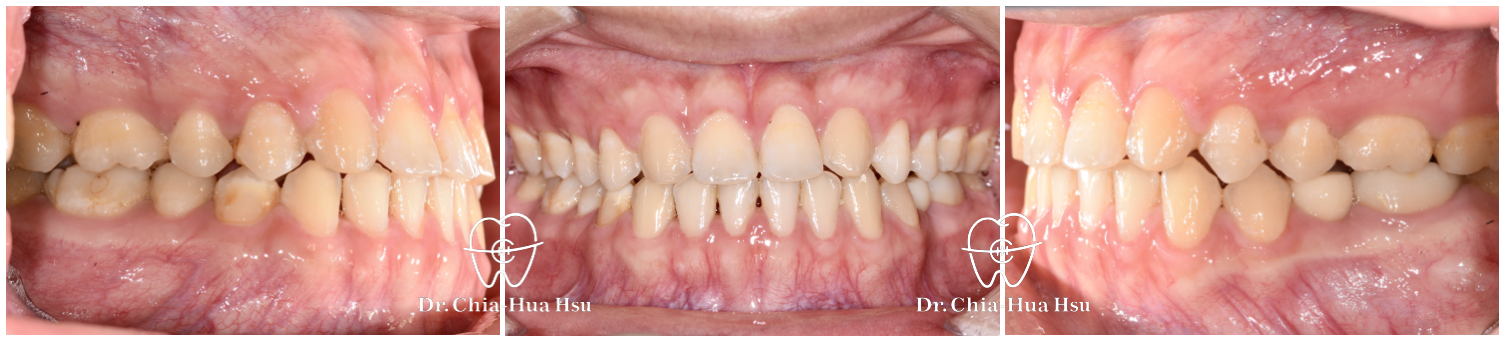

• 病患主訴:在意門牙牙縫和齒列不正。

• 問題分析:患者除了門牙牙縫、齒列不正問題,有先天性缺失上顎雙側側門牙兩顆以及左下第二小臼齒,並且左下方有滯留的乳臼齒,治療難度高。

• 治療方式:使用傳統金屬矯正器,並搭配拉口內橡皮筋的方式來讓上顎後排牙齒往前移動,以關閉缺牙縫隙。

• 治療結果:改善缺牙、縫隙,以及上下顎咬合關係,左下乳臼齒拔除後以一顆植牙重建。